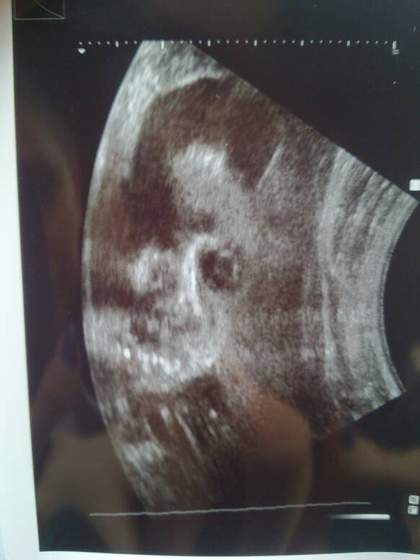

Ja juz po :-D super babka usg z 40 min trwało wszystko sprawdziła wszystko jak najbardziej ok mała BO NA 100% DZIEWCZYNKA! :-D mniejsza wychodzi 24 tydzień 724g

Ale przyrost wagi prawidłowy wiec taki jej urok... Według wagi termin na 9 lutego :-o :-P

Wstawiam zdjęcie buźki nie wiem czy coś zobaczycie :-P